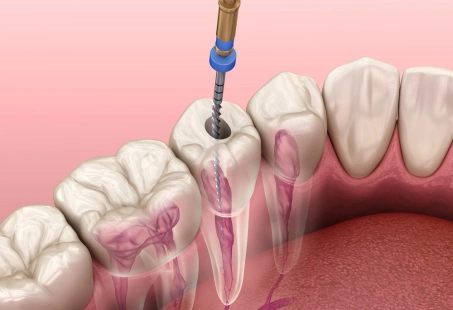

Root Canal Treatment (RCT) is a dental procedure used to treat infected or damaged pulp inside a tooth. The treatment saves the natural tooth, eliminates infection, and prevents further dental problems.

Start from. Rp. 1.500.000